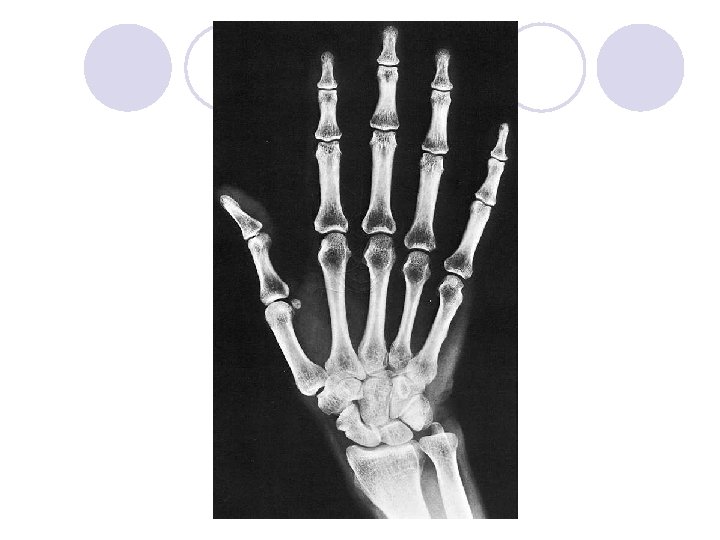

Ruka - MANUS l Kosti zápěstí – OSSA CARPI l Kost loďkovitá – OS NAVICULARE l Kost poloměsíčitá – OS LUNATUM l Kost trojhranná – OS TRIQUETRUM l Kost hráškovitá – OS PISIFORME l Kost mnohohranná větší – OS TRAPEZIUM l Kost mnohohranná menší – OS TRAPEZOIDEUM l Kost hlavatá – OS CAPITATUM l Kost hákovitá – OS HAMATUM

Ruka - MANUS l Kosti záprstní – OSSA METACARPI l Záprstní kost – OS METACARPALE I – V l Kosti prstů ruky – OSSA DIGITORUM MANUS l Články prstů – PHALANGES l Palec má dva, ostatní prsty mají po třech